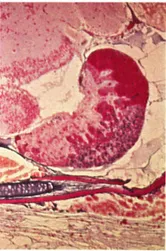

Fig. 2 Poecilia latipinna. Sagittal section through pituitary of a female fish, anterior to the right. The mass of prolactin cells (bright red) together with the bands of colorless ACTH cells projecting into the neurohypophysis posteriorly form the rostral pars distalis. In the proximal pars distalis, note the ventral mass of blue gonadotrops and the dorsally projecting fingers of orange growth hormone cells, mixed with a few blue TSH cells. The pars intermedia is small in cyprinodonts and forms a thin ventral rim to the posterior neurohypophysis, which contains large Herring bodies (neurosecretory material). Azan.